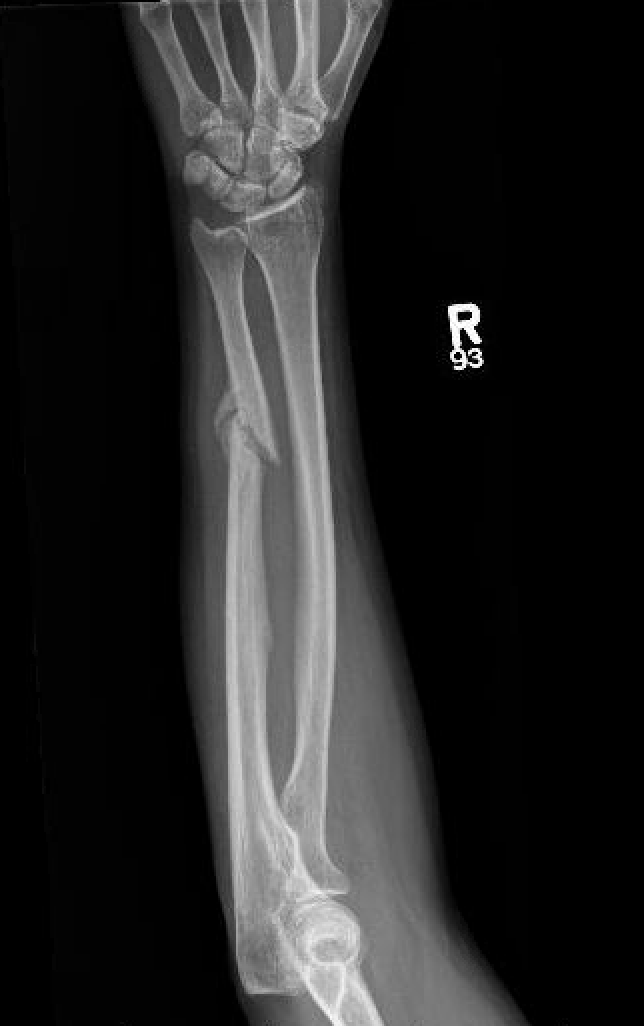

Isolated ulna fractures

Mechanism

Night stick injury - direct blow or trauma to ulna

Location

Distal 1/3

Midshaft / middle 1/3

Proximal - beware Monteggia / radial head dislocation